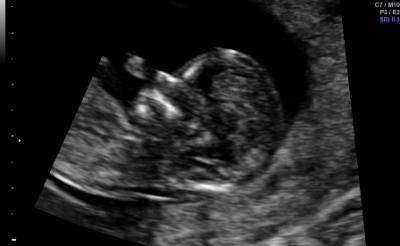

Hallo ihr lieben, ich hab mich schon lange nicht mehr gemeldet, aber alles regelmäßig mitgelesen. Ich hatte seit 5 wochen endlich mal wieder FA Termin, ich war schon so beunruhigt. Aber alles in Ordnung, alles wie es sein soll. laut FÄ ist der "Geschlechtshöcker" in sehr flachem Winkel was laut ihr zu 80% auf ein Mädchen hindeutet.... ich würd mich freuen bin einfach heilfroh dass alles gut aussieht und hoffe dass die Übelkeit nun auch bald aufhört. nächster Termin erst wieder in 5 Wochen, davor zum Glück noch in den Urlaub

Bild zu wiedermal melden - Forum für Januar - Mamis